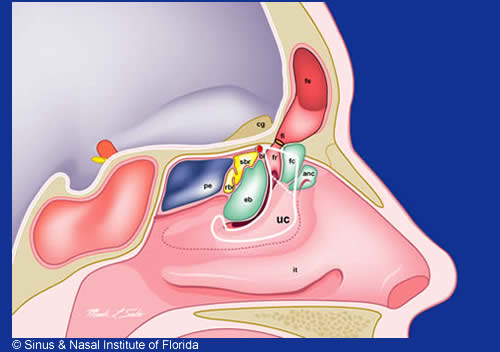

Sinus Nasal Institute Of Florida

Sinus Nasal Institute Of Florida